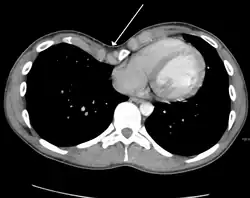

A pleural effusion is an accumulation of fluid inside the pleural space. If this collection of fluid gets large enough, it can also push structures in the chest away from it and cause a mediastinal shift. However, a pleural effusion can also pull the mediastinal structure towards itself. If this is the case, then there is an underlying condition causing the collapse of the lung on that side. An example is a tumor obstructing a bronchus and causing lung collapse and pleural effusion.[3]

Masses such as tumors can also cause compression and displacement of mediastinal structures. There are various mediastinal tumors, and they are classified by their location in the chest. Notable examples include germ cell tumors and lymphomas.[12] Teratomas are a class of germ cell tumors that arise in the chest due to failure of germ cell migration during development. They can expand to large sizes and cause hemoptysis and pleural effusion. Radiographic features of teratomas typically include fluid and fat but also muscle, teeth, and bones inside the mass.[13]